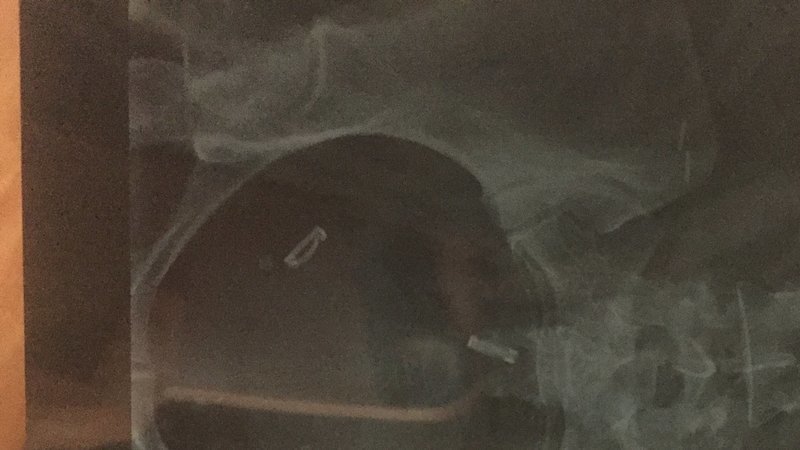

La méthode contraceptive des clips de Filshie® (et/ou Clips Wolf®/Hulka®)  est un dispositif médical.

"Les clips agissent en bloquant l'alimentation sanguine d'une petite section des trompes. Les tissus cicatriciels ou fibreux empêchent ensuite la fécondation de se produire. Les deux types de clips les plus utilisés sont le clip Filshie en titane et le clip Wolf en plastique (aussi connu sous le nom de clip Hulka). Les clips sont faciles d'emploi, mais chaque type requiert un applicateur d'un modèle spécial". Extrait vu sur caducee.net.